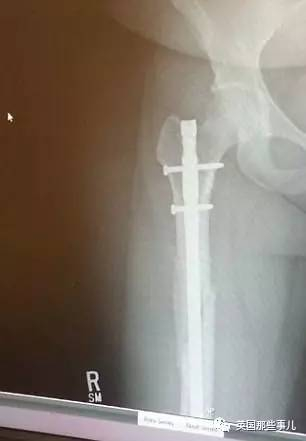

出院时,由于多处骨折,她的脚踝、臀部、膝盖上分别被打上了2个钢钉……